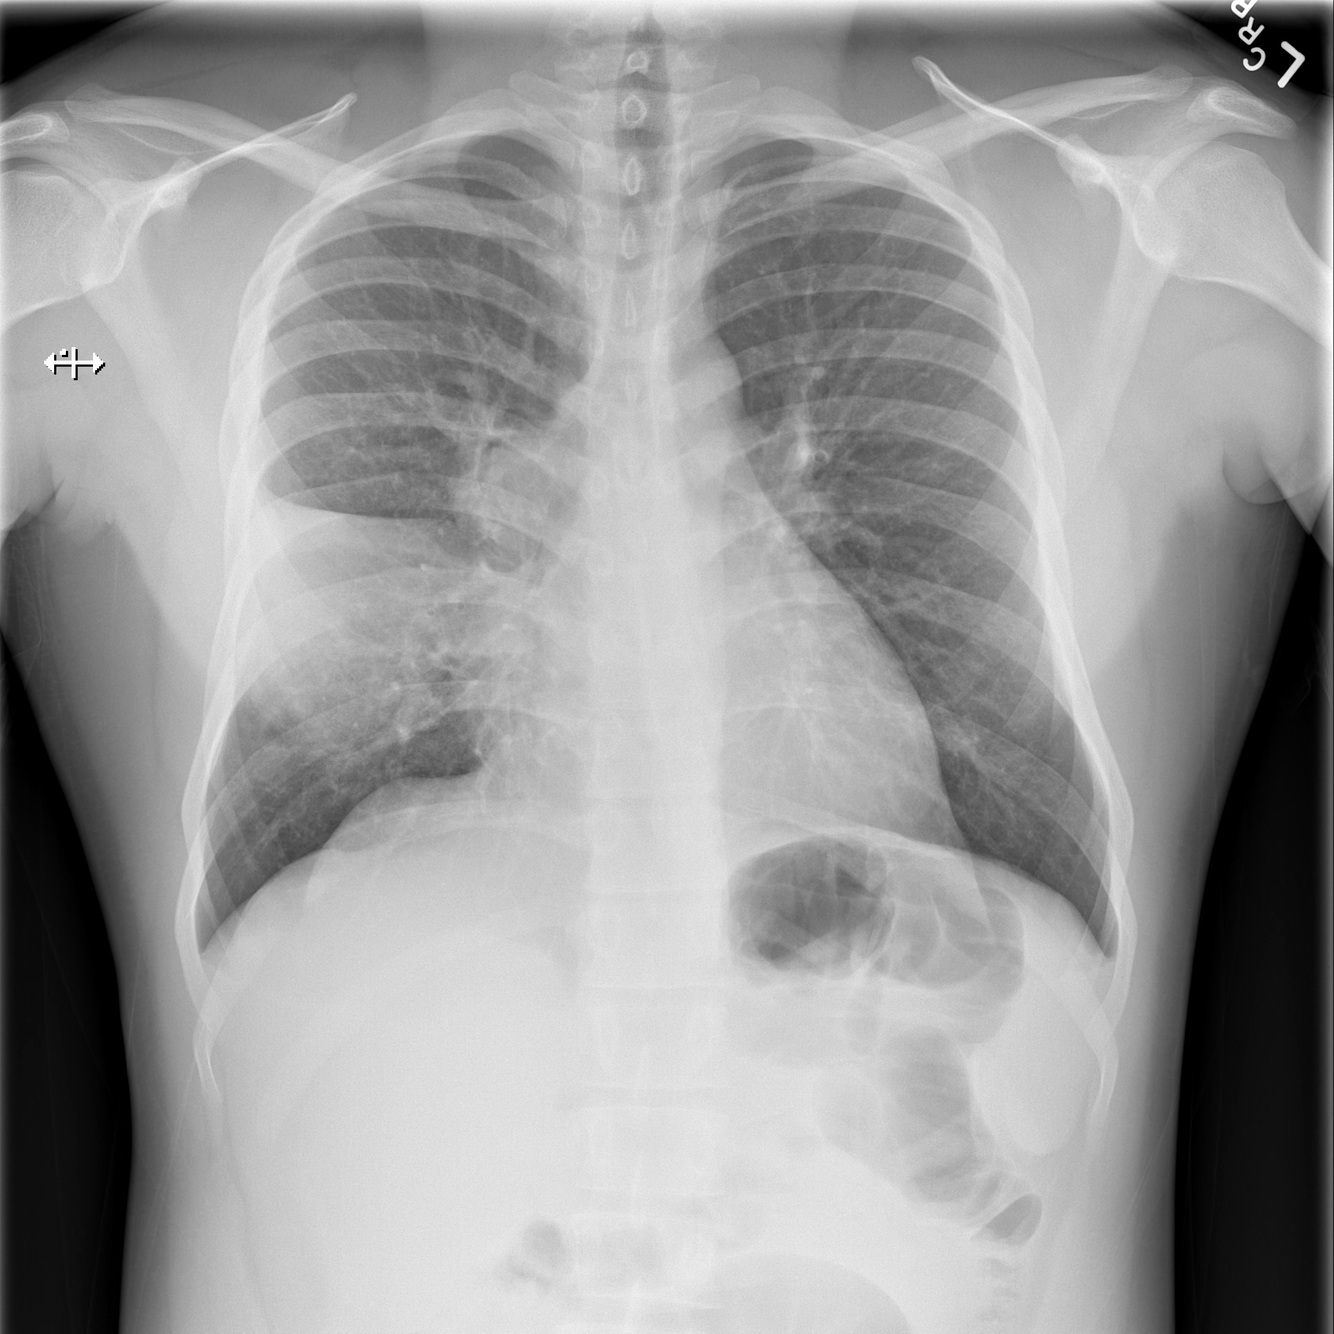

BHL

Sarcoidosis, malignancy, TB

Ask about joint pain, cough